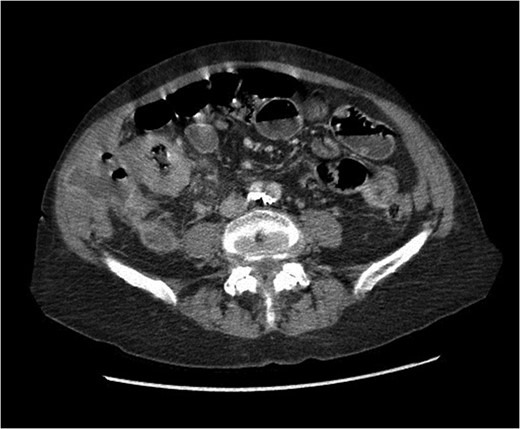

At presentation her vital signs were stable. Abdominal exam revealed exquisite tenderness in the right lower quadrant, with no evidence of digital clubbing. Blood-work revealed an elevated WBC of 15.6. A CT scan demonstrated a 4.3 cm annular mass within the cecum, suspicious for a primary colonic malignancy, as well as an 8.6 × 8.2 cm2 lobulated gas-containing abscess with extension in to the lateral abdominal wall (Figs 4 and 5).

Coronal view of abdominal CT scan showing cecal mass with evidence of perforation.